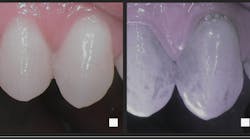

Preliminary observations suggest that antibacterial dual light therapy such as Lumoral (not yet available in the US) might be an important tool in the armory for oral mucositis treatment. Confirmation studies shall be set up to further investigate the effectiveness of the novel approach, and Dr. Waltimo says a new doctoral dissertation study will commence at the University of Helsinki in the spring of 2024.